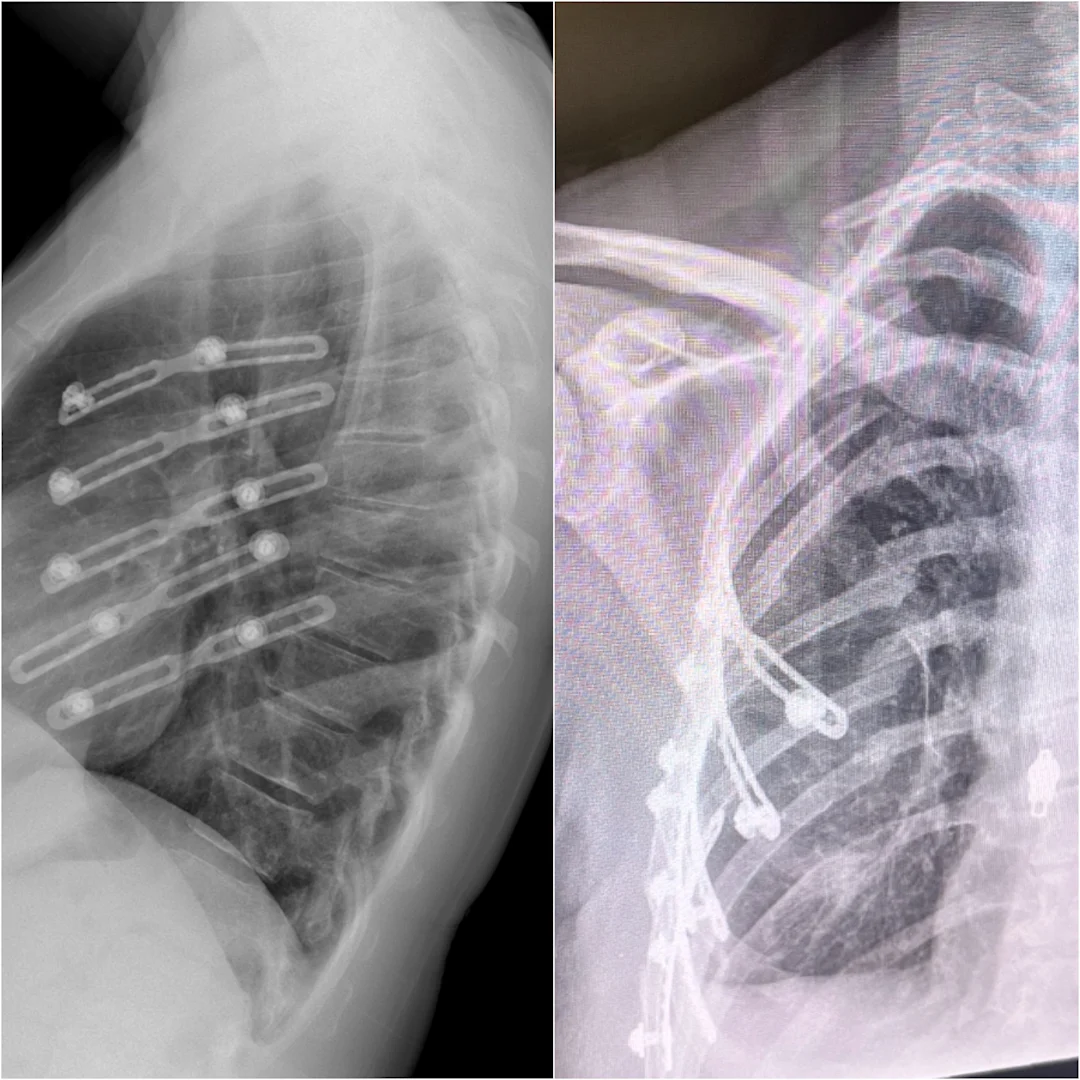

Dr. Haluck, along with Dr. Donald Mackay, professor of surgery, neurosurgery, and orthopedics and rehabilitation, and Dr. Peter Dillon, former chief of surgery and current executive vice president and chief clinical officer at Penn State Health, had an idea. What if they could attach a metal plate to the inner surface of the broken rib, instead of the outer surface?

“The ribs are like a stone bridge. They do their job as long as the arch is intact, but as soon as you break the arch, it doesn’t function anymore,” Haluck said. By positioning the plate on the underside of the rib, it’s like pushing the stone back up and into the arch, restoring the arch’s structure.

Their groundbreaking invention became RibFix Advantage—the first rib fixation system cleared by the Food and Drug Administration (FDA) and used to help patients recover from broken ribs.

X-ray images show the innovative RibFix Advantage system in place, which helped repair Nancy Rehm's shattered ribs and accelerate her recovery.

RibFix is a true medical breakthrough and is changing how doctors treat potentially life-threatening chest injuries. This less invasive method translates to fewer complications, reduced risks, and shorter hospital stays, giving patients a better path to recovery. In many cases, the procedure takes less than an hour and requires only three small incisions along the chest.